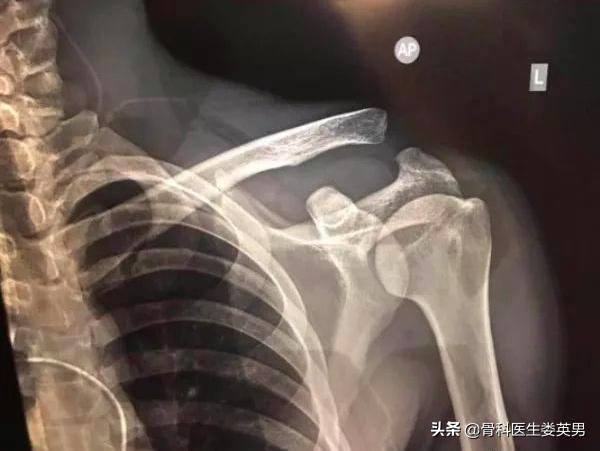

武磊左肩关节究竟出了什么问题?

那么,武磊的左肩究竟是受了多严重的伤,竟然严重到要靠着止痛药和打封闭来强撑。

根据媒体报道:武磊的伤情确认为是严重的"三型肩锁脱位"。

人体肩关节主要由两个关节组成,一个是肩关节,一个是盂肱关节。肩锁关节属平面关节,顾名思义,是连接肩峰和锁骨的关节,平躺在床上,沿着锁骨往外摸,摸到一个和肩峰的小凹陷,这就是肩锁关节。

它的关节囊比较松弛,所以主要靠肩锁韧带和喙锁韧带来维持稳定。这几根韧带就像绳子一样,牢牢地把锁骨和身体的其它骨骼连在了一起。

事实上,我们常说的肩锁关节损伤就是这些韧带的损伤,它临床比较常见,约占肩部损伤脱位的12%。而直接*力暴**!则是能够损伤这些韧带的最主要的原因。面对如此强劲的韧带,想要损伤它,只可能是更加直接、凶猛的*力暴**。武磊的受伤就是左侧肩关节肩峰直接撞击地面。

III型损伤的战况就比较惨烈了,肩锁韧带早就断的不成样子,喙锁韧带终于也扛不住这么猛烈的攻击,被撕裂了。锁骨前不连肩峰,下不着肩胛骨,无处依靠。

话归正题,武磊这次的受伤是"三度肩锁关节脱位"这种损伤会发生三角肌和斜方肌肌纤维撕裂以及喙锁韧带断裂。这样的伤无法自愈,必须进行手术,康复期则大约需要3个月左右。如果不治疗的话,会对患者的侧肩功能造成严重影响,主要影响患肢外展和前后伸的功能。

从下图可以看出,武磊在受伤后左侧肩关节疼痛、肿胀、肩关节无法正常活动,引起肩锁关节不稳定,锁骨外侧端较高,呈"台阶样畸形";锁骨外端浮动感,用手指按下去会弹起来,也就是常说的"琴键征",这是在Ⅲ型肩锁关节脱位的典型表现。